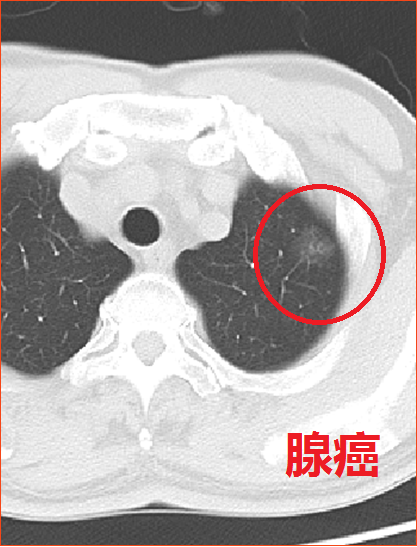

哪些肺结节恶性概率大?

简单来说,结节越大,恶性概率越大。从CT影像来看,混合性磨玻璃结节恶性概率高,如结节有分叶征、毛刺征、血管征等征象也要高度警惕。另外还要结合患者的年龄、吸烟史、家族史等因素一起综合分析结节性质。